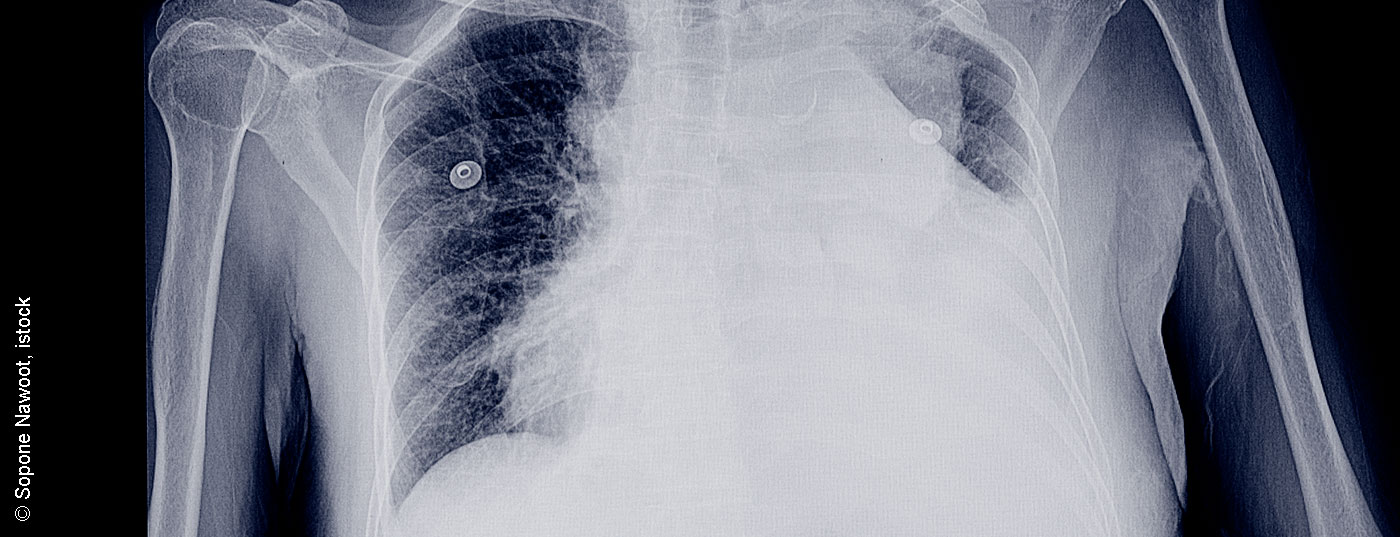

pleuraerguss_istock-952689296

• Vom sinnvollen diagnostischen Algorithmus zur Guideline-konformen Therapie

Pleuraerguss – Diagnose und Therapie

Pleuraergüsse sind häufige Erkrankungen und in vielen Fällen Begleitsymptom einer Vielzahl von Krankheiten. Eine exakte Diagnose ist für die weitere Zuordnung und auch für die Therapie entscheidend. Einige wichtige Studien der letzten Jahre sind in die internationalen Empfehlungen eingeflossen.